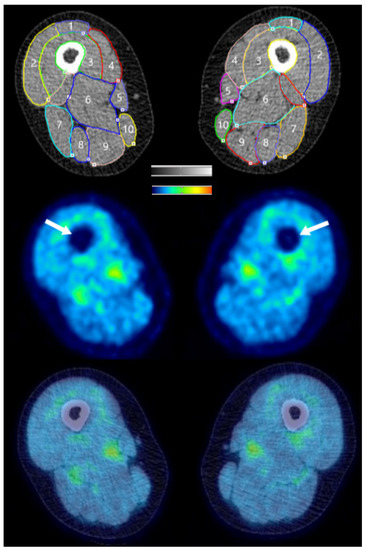

2.5. PET/CT Imaging

3.1.1. Standardized Uptake Values (SUVs)

3.2.1. Standardized Uptake Values (SUVs)

3.3.1. Standardized Uptake Values (SUVs)

3.4.1. Standardized Uptake Values (SUVs)